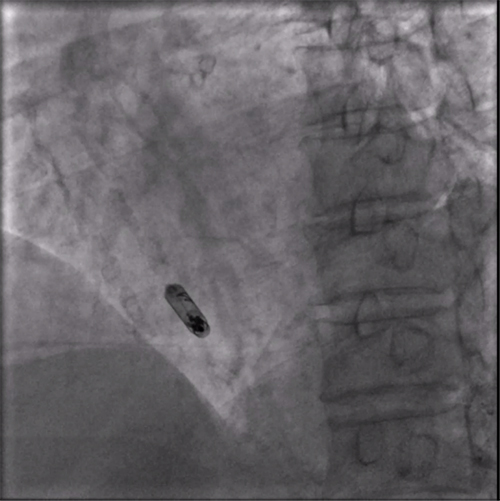

植入后右前斜

植入后左前斜

术后程控报告

术后第二天程控结果显示:起搏参数良好,电池预估寿命:22.6年,充分显示新型主动固定螺旋无导线起搏器大电池长寿命特点。